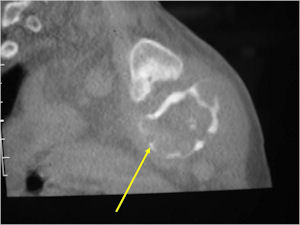

Plain X-rays:

- Geographic, circumscribed lesion usually around 5cm in size.

- There may be expansion of bone, cortical thinning and cortical breakthrough. A soft tissue mass may accompany this lesion but the soft tissue component is usually contained by the periosteum.

- The periosteum remains intact around the soft tissue component. Might need a CT scan to detect the subtle calcification (Egg Shell Rim of Calcification) associated with an intact periosteal reaction

- The lesion may be entirely radiolucent but usually shows some degree of mineralization. Mineralization may appear stippled like cartilage but do not see chondroid pathologically. Mineralization is sometimes better detected on a CT scan rather than an x-ray.

- Usually less surrounding sclerosis than an osteoid osteoma.

- Arise from the Diaphysis (75%) more commonly than Metaphyseal (25%)

- 4 cm to 6 cm in size

CT Scan:

- More useful for detecting mineralization and evaluating extent of bone destruction than plain X-ray